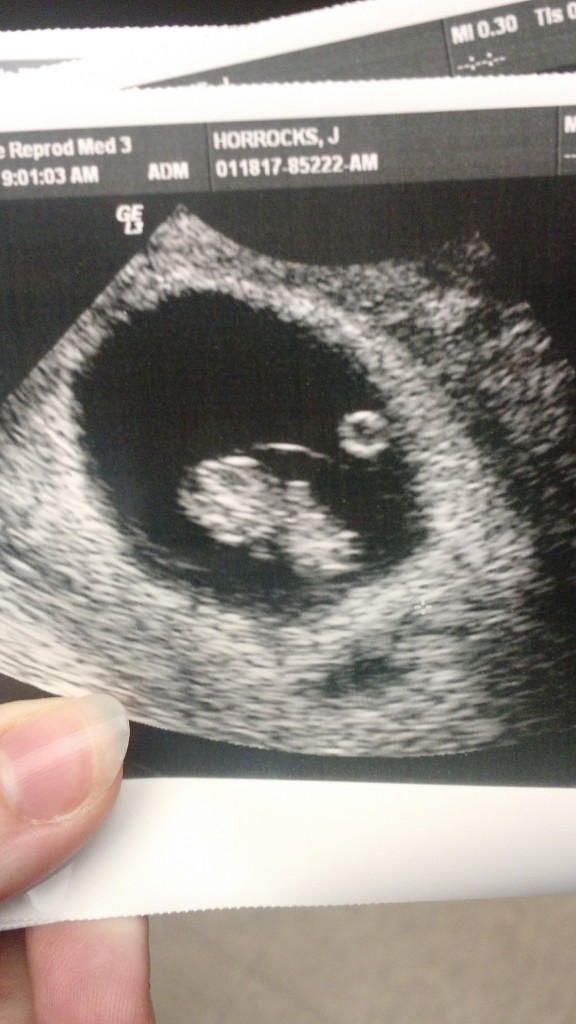

Ultrasound Jan 18th

Since I have a history of miscarrage, I was monitored weekly with ultrasounds and bloodwork until I was around 9 weeks along. Then I switched to my regular OB’s office. On my first visit my OB came in laughing. He looked at me and said “If I remember right, you were in a lot of pain with your last pregnancy, and said that it was the last one.” I smiled and said that was right. He then told me that since I had lost so much weight that hopefully I would not have as much pain this time around. He cracked a few jokes while I was in the office and I left laughing. I really LOVE my OB.